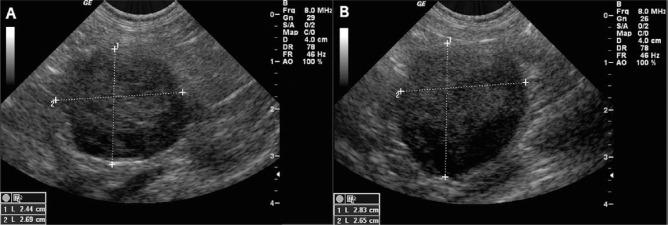

A 10-year-old, 5.1 kg (11.2 lb), male castrated cat was presented with signs of lethargy and decreased appetite at home after being previously healthy. Serum biochemical analysis identified normokalemia (5.1 mmol/l; reference interval [RI] 3.4-5.6 mmol/l) and severe hyponatremia (123 mmol/l; RI 145-158 mmol/l), with an Na/K ratio of 24 (RI 32-41). Baseline serum cortisol was low to normal, but serum aldosterone was markedly decreased with a pre-adrenocorticotropic hormone stimulation concentration of 13 pmol/l (RI 194-388 pmol/l) and post-adrenocorticotropic hormone stimulation concentration of 21 pmol/l (RI 277-721 pmol/l). Hematologic and biochemical analyses were otherwise unremarkable. Abdominal ultrasound revealed bilaterally enlarged adrenal glands with no other abnormalities noted; thoracic radiographs also did not identify any signs of metastasis. Fine-needle aspiration was strongly suggestive of lymphoma of the adrenal glands, and PCR for antigen receptor rearrangement was positive for B-cell clonal expansion; based on these findings, a diagnosis of primary adrenal B-cell lymphoma was made. Stable disease was achieved for a short period of time following vincristine, cyclophosphamide, prednisolone and fludrocortisone therapy, followed by progressive adrenal enlargement and electrolyte derangements that responded to neither doxorubicin nor adjustments in fludrocortisone dosage. Ultrasonographic metastasis was not identified at any time, and other organ derangements were not noted on hematologic or biochemical analyses. The cat was euthanized 55 days after initial presentation.

一只10岁、体重5.1千克(11.2磅)的去势雄性猫,此前健康,在家中出现嗜睡和食欲减退的症状。血清生化分析显示血钾正常(5.1毫摩尔/升;参考区间[RI] 3.4 - 5.6毫摩尔/升),严重低钠血症(123毫摩尔/升;RI 145 - 158毫摩尔/升),钠/钾比值为24(RI 32 - 41)。基础血清皮质醇水平低至正常,但血清醛固酮显著降低,促肾上腺皮质激素刺激前浓度为13皮摩尔/升(RI 194 - 388皮摩尔/升),促肾上腺皮质激素刺激后浓度为21皮摩尔/升(RI 277 - 721皮摩尔/升)。血液学和生化分析其他方面无异常。腹部超声显示双侧肾上腺肿大,未发现其他异常;胸部X光片也未发现转移迹象。细针穿刺强烈提示肾上腺淋巴瘤,抗原受体重排的聚合酶链反应显示B细胞克隆性扩增呈阳性;基于这些发现,诊断为原发性肾上腺B细胞淋巴瘤。长春新碱、环磷酰胺、泼尼松龙和氟氢可的松治疗后短期内病情稳定,随后肾上腺逐渐增大,电解质紊乱加重,多柔比星治疗及氟氢可的松剂量调整均无效。在任何时候均未发现超声检查提示的转移,血液学或生化分析也未发现其他器官紊乱。该猫在初次就诊后55天实施安乐死。